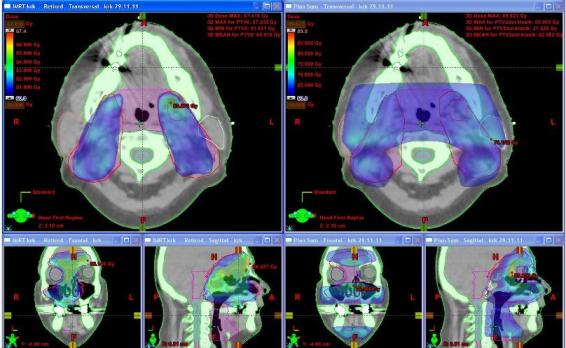

Obr. č. 1: Distribuce dávky (60 Gy a více) v transverzálním skenu v oblasti horních krčních uzlin a ve frontální a sagitální rekonstrukci u techniky IMRT (vlevo) a u 3DCR (vpravo).

Na frontální rekonstrukci plánu pro IMRT (obr. č. 1 vlevo) je patrné dobré pokrytí tumoru v oblasti vnitřní orbity vpravo a přilehlé nosní dutiny zvolenou dávkou na rozdíl od 3DCR (obr. č. 1 – vpravo), kde je toto pokrytí nedostatečné. Na frontálních i sagitálních rekonstrukcích (obr. č. 1 vlevo) v barevném mapování dávky je vidět eskalovanou dávku v místech tumoru (zelená barva).

Obr. č. 2: Distribuce dávky (63 Gy a více – zelená, 60 Gy a více modrá ) v transverzálním skenu v oblasti orbity, dutiny nosní a sfenoidální, ethmoidů a ve frontální a sagitální rekonstrukci u techniky IMRT (vlevo) a u 3DCR (vpravo).